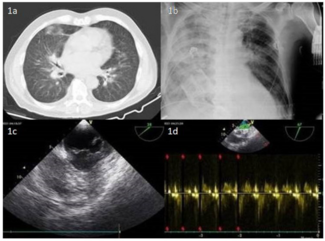

A 72-year-old man with chronic obstructive pulmonary disease (COPD) complained of worsening dyspnea. Physical examination revealed a soft systolic murmur best heard at the apex, third cardiac sound, hypoventilation of the right lung, and...